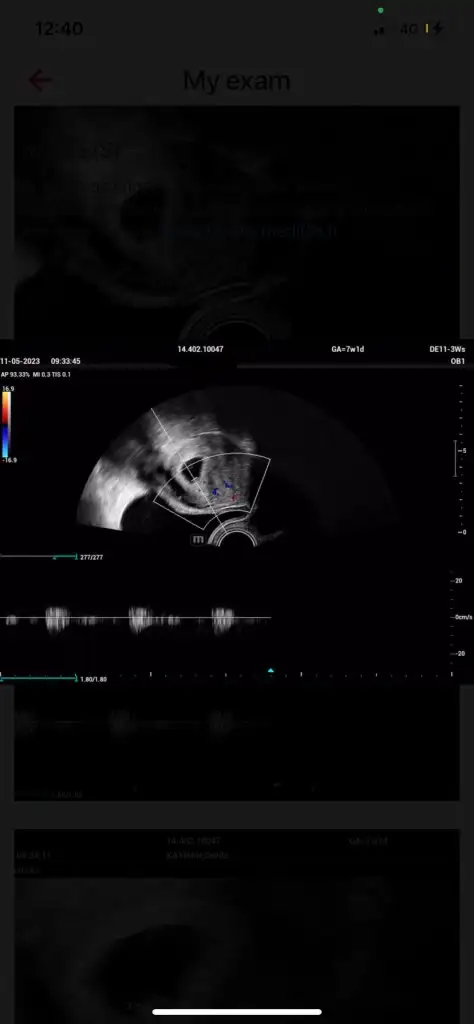

Bugün bebeği ve kalp atışını gördük çok şükürBen direk alttan muayene etmesini istedim çünkü karından çok küçük olduğu için görünmüyorlar genelde aslında aletlerle de alakalı iyi bir aletse bence karından da rahat görünüyor iyi hastanelerin. Evet benim de bildiğim kadarıyla o yuvarlak siyah halkın etrafındaki beyaz Çember yok kesesi deniliyor muş ben de çok bilmiyorum benim de bundan önce bir kimyasal bir normal kaybım olmuştu. O yüzden biraz tedirginim ama inşallah güzel sonuçlar alacağız güzel düşünmek lazım sizinde güzel haberleriniz olur mutlaka buradan haberleşelim

7+1 sanırım ultrason da öyle görünüyorMerhaba kaçıncı haftada gördünüz

canım ben de gittim bugun bebeği de gördüm kalbini de dinledim 7+6ydım doktor 7haftalık geç döllenmedir sorun yok dedi gayet iyi kalbi kese falan dedi karından göründü zaten cok sükür insallah hepimiz de sağlıklıca kucagımıza alırızHadi diğerinin de kalp atışını görürsün inşallahbenim de kan pıhtılaşmam varmış. 3-4 gün önce geldi sonucum. Aspirin başlayacağım bu akşam. Karından görünebiliyorsa sizin süper. Çünkü benim karından baktı. Bsey göremiyorum. Çok kötü. Üzgünüm falan dedi. Çok kötü oldum ben de. Sonra vajinalden bakınca gördü çok şükür